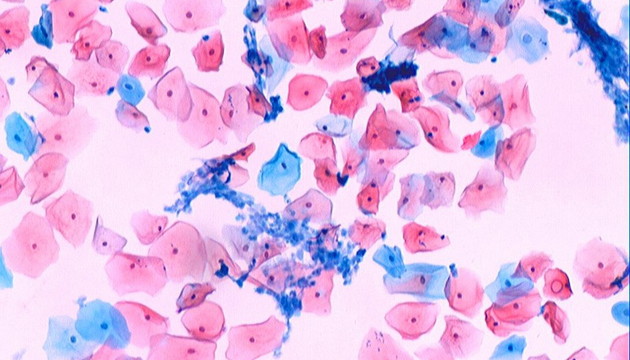

病理學按觀測對象分器官、組織、分子病理學。器官病理學依賴肉眼及顯微鏡,確定病變性質。組織病理學則通過切片染色觀察細微病變,常用HE、PAS、革蘭氏、巴氏及油紅O染色。分子病理學分析蛋白或基因表達,用于疾病進程與藥效評估,常用IHC免疫組化定蛋白質,FISH技術檢測特定基因片段,助力精準醫療。

免疫組化病理,明美ML51-M搭配MSX2拍攝